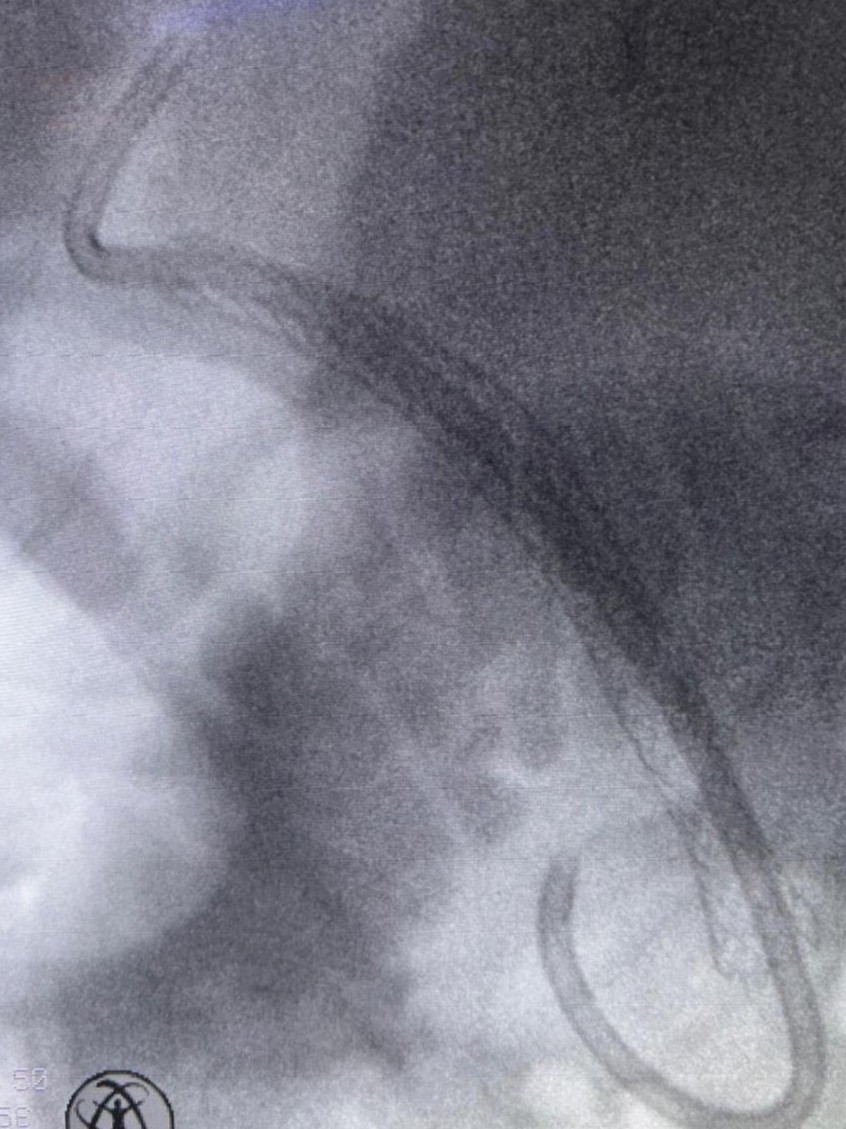

Magnetic resonance cholangiography (MRCP) revealed mild intrahepatic bile duct dilatation in both hepatic lobes, a tight anastomotic stricture of the common bile duct, and dilation of the common bile duct above the bilio-biliary anastomosis up to 11 mm (Fig. 1).

Selective cannulation of the common bile duct (CBD) was achieved using a 0.025-inch guidewire-assisted sphincterotome. Injection of radiopaque contrast revealed a tight mid-choledochal stricture, associated with mild intrahepatic bile duct dilatation. The CBD was dilated above the biliary anastomosis up to 11 mm, with the distal CBD measuring 6 mm. A wide endoscopic sphincterotomy was performed, and attempts were made to advance a 0.025-inch guidewire—both angled and straight—into the intrahepatic biliary tree; however, the anastomotic biliary stricture could not be traversed. Subsequently, the SpyGlass cholangioscope was introduced, enabling direct visualization of the biliary anastomotic stricture and successful passage of the 0.025-inch guidewire across the stenotic segment into the intrahepatic bile ducts. Balloon dilation of the biliary stricture was then performed using a 6/40-mm balloon under combined cholangioscopic and fluoroscopic guidance. Following endoscopic bilioplasty, the cholangioscope advanced through the stricture easily, and tissue samples were collected from the choledochal anastomosis (Fig. 2 and Video 1). A fully covered 8/80mm biliary self-expanding metal stent (SEMS) was subsequently placed, followed by insertion of a 10 Fr/5cm double-pigtail plastic biliary stent through the SEMS to prevent migration of the fully covered stent (Fig. 3, Fig. 4).